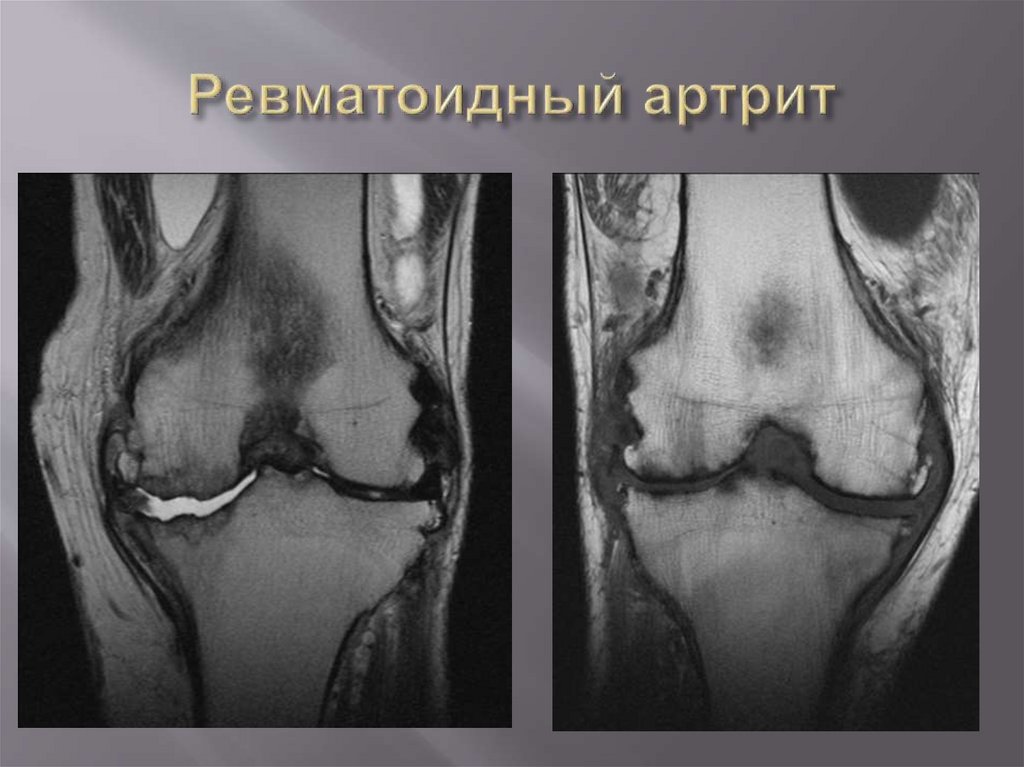

Эрозия

суставной

поверхности